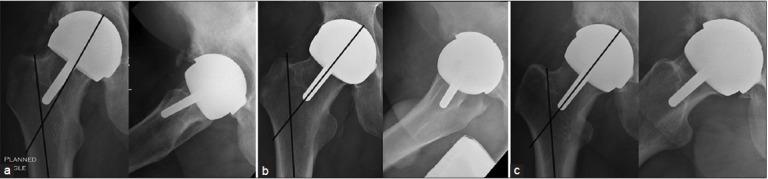

Between December 2004 and December 2008, 213 consecutive hip resurfacings were performed by a single surgeon. The first 17 (Cohort 1) and the last 9 (Cohort 2) hip resurfacings were performed using a conventional guidewire alignment jig. In 187 cases, the femoral component was implanted using the imageless computer navigation. Cohorts 1 and 2 were compared for femoral component alignment accuracy.

All components in Cohort 2 achieved the position determined by the preoperative plan. The mean deviation of the stem-shaft angle (SSA) from the preoperatively planned target position was 2.2° in Cohort 2 and 5.6° in Cohort 1 (P = 0.01). Four implants in Cohort 1 were positioned at least 10° varus compared to the target SSA position and another four were retroverted.

2004年12月至2008年12月期间,由一名外科医生连续进行了213例髋关节表面置换手术。前17例(队列1)和后9例(队列2)使用传统导丝对线夹具进行髋关节表面置换。187例使用无影像计算机导航植入股骨假体。比较队列1和队列2中股骨假体对线的准确性。

队列2中的所有假体均达到术前计划确定的位置。队列2中假体柄-轴角(SSA)与术前计划目标位置的平均偏差为2.2°,队列1为5.6°(P = 0.01)。队列1中有4个假体相对于目标SSA位置内翻至少10°,另有4个假体向后倾斜。